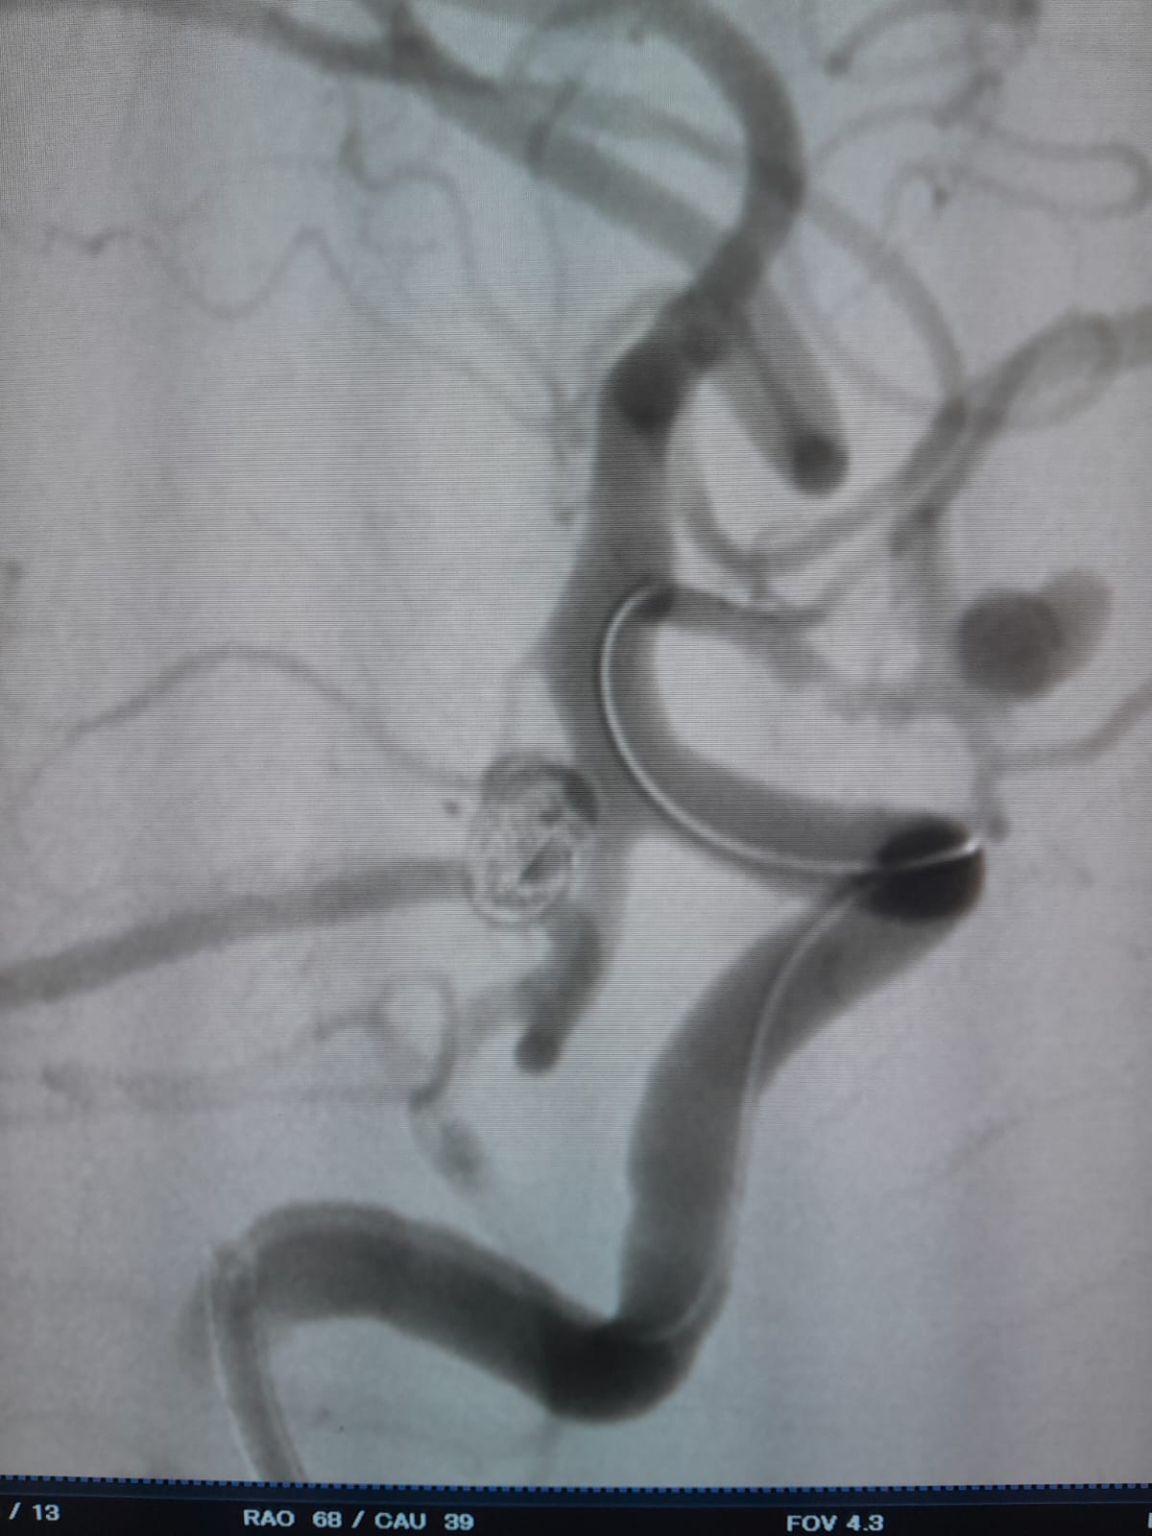

El paciente fue diagnosticado con un aneurisma de la arteria comunicante anterior (AComA) recién descubierto y un aneurisma de la arteria comunicante posterior (PComA) que había sido tratado previamente con embolización con espiral. Las imágenes de seguimiento revelaron un relleno residual en el aneurisma PComA, que requirió una intervención adicional.

Aneurisma de arteria comunicante anterior

Se estableció el acceso vascular y el equipo luego navegó con éxito el®Microcatéter desechable (TJMC14) al sitio objetivo. La embolización se realizó utilizando tres Perdenser®Sistema de bobina embólica (TJCST4.508-3D, TJCST0306-3D, TJCST0206-3D) desplegado con el Deromper®Controlador de desprendimiento de bobina (TJCDC).

Aneurisma de la arteria comunicante posterior (re-tratamiento)

Durante el seguimiento, se observó llenado residual en el aneurisma de la arteria comunicante posterior tratado previamente. El equipo reingresó al sitio usando el sistema de acceso a través de la aplicación de la tarjeta de crédito®Microcatéter desechable (TJMC18 Plus) e implementado con éxito un Nuva®Desviador del flujo (TJED-D-4.5-16), que demostró aposición ideal de la pared y desviación excelente del flujo, llevando a los resultados altamente satisfactorios del tratamiento.